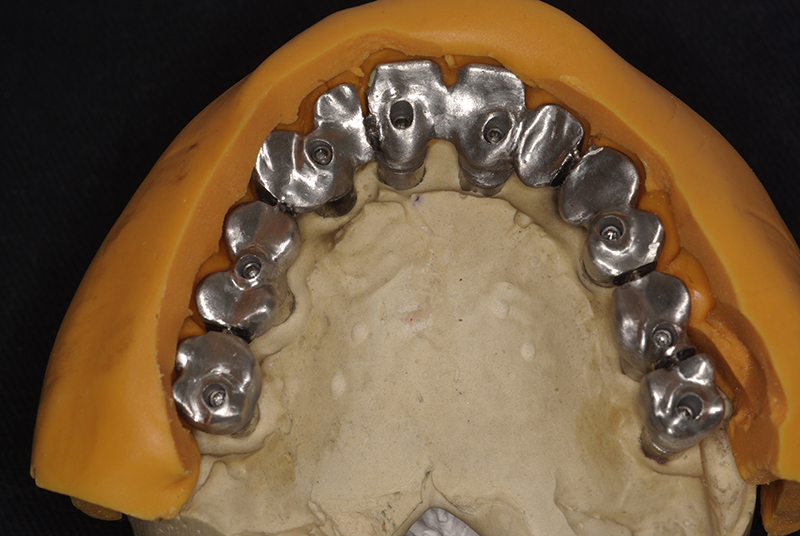

- Planejamento Digital: Com o auxílio de tecnologias como tomografias e softwares 3D, a posição dos implantes é planejada com precisão.

- Cirurgia de Instalação dos Implantes: Os implantes são fixados no osso maxilar ou mandibular, proporcionando uma base sólida para a prótese.